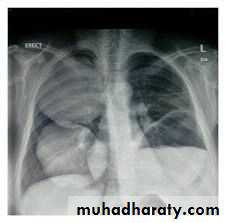

Patient with fever, rigor and dyspnea